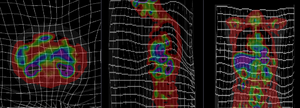

PET overlay ; BSpline registration of full volumes. 11 x 11 x 7 gridPET overlay ; BSpline registration of full volumes. 11 x 11 x 7 grid grid overlay showing BSpline deformation grid overlay showing BSpline deformation